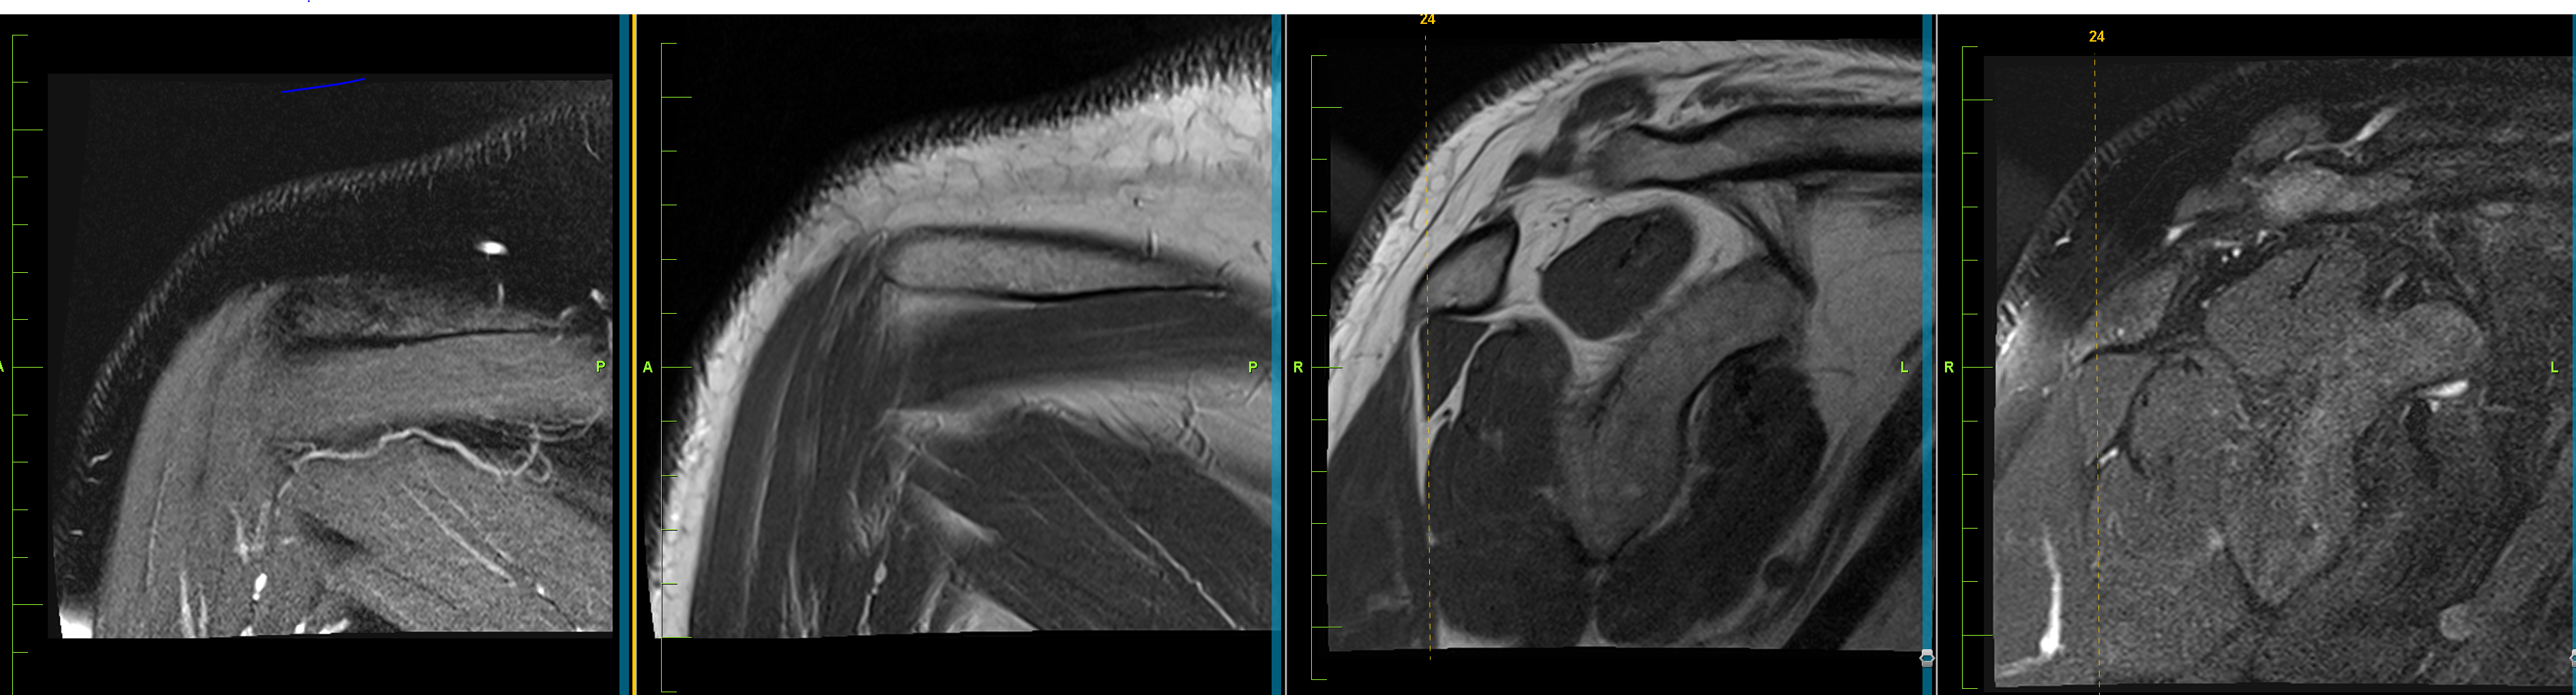

Dear colleagues, I’d appreciate your thoughts on a chronic knee pain case with MRI findings of thickened cartilage in the tibia and femur (suspected congenital), irregular signal changes with cystic alterations, and mild downward-facing medial/lateral tibial joint surfaces. ACL, PCL, collateral ligaments, quadriceps tendon, and patellar ligament: Normal. Minimal posterior degeneration in the medial meniscus.

![]()

Congenital Cartilage Thickening or Syndrome? Read More »